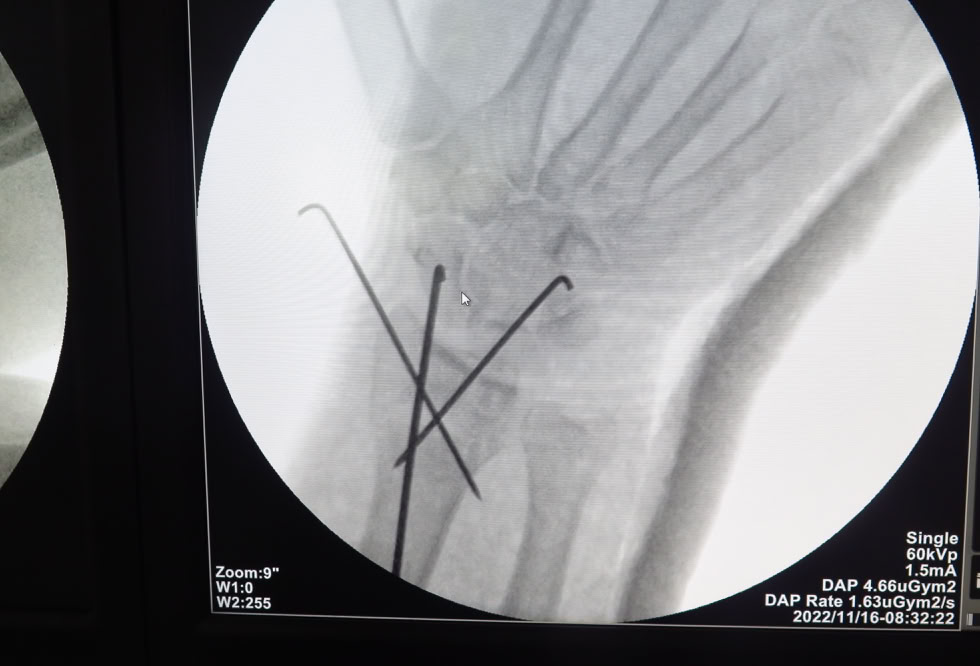

Recibimos la visita de un traumatologo que trabaja en un hospital de Duala y que se desplazó hasta Dschang para que le tratáramos nosotros las lesiones que sufrió al caerse por unas escaleras, “no se fiaba de sus compañeros de hospital”. Una fractura de la extremidad distal del radio que solucionamos con una reducción y estabilización con agujas K (no tenemos placas volares) con excelente resultado  y una fractura diafisaria de humero que solucionamos con unos clavos elásticos (no tenemos clavos de humero). El paciente estaba muy satisfecho a pesar de la parálisis radial que se produjo al fracturarse.